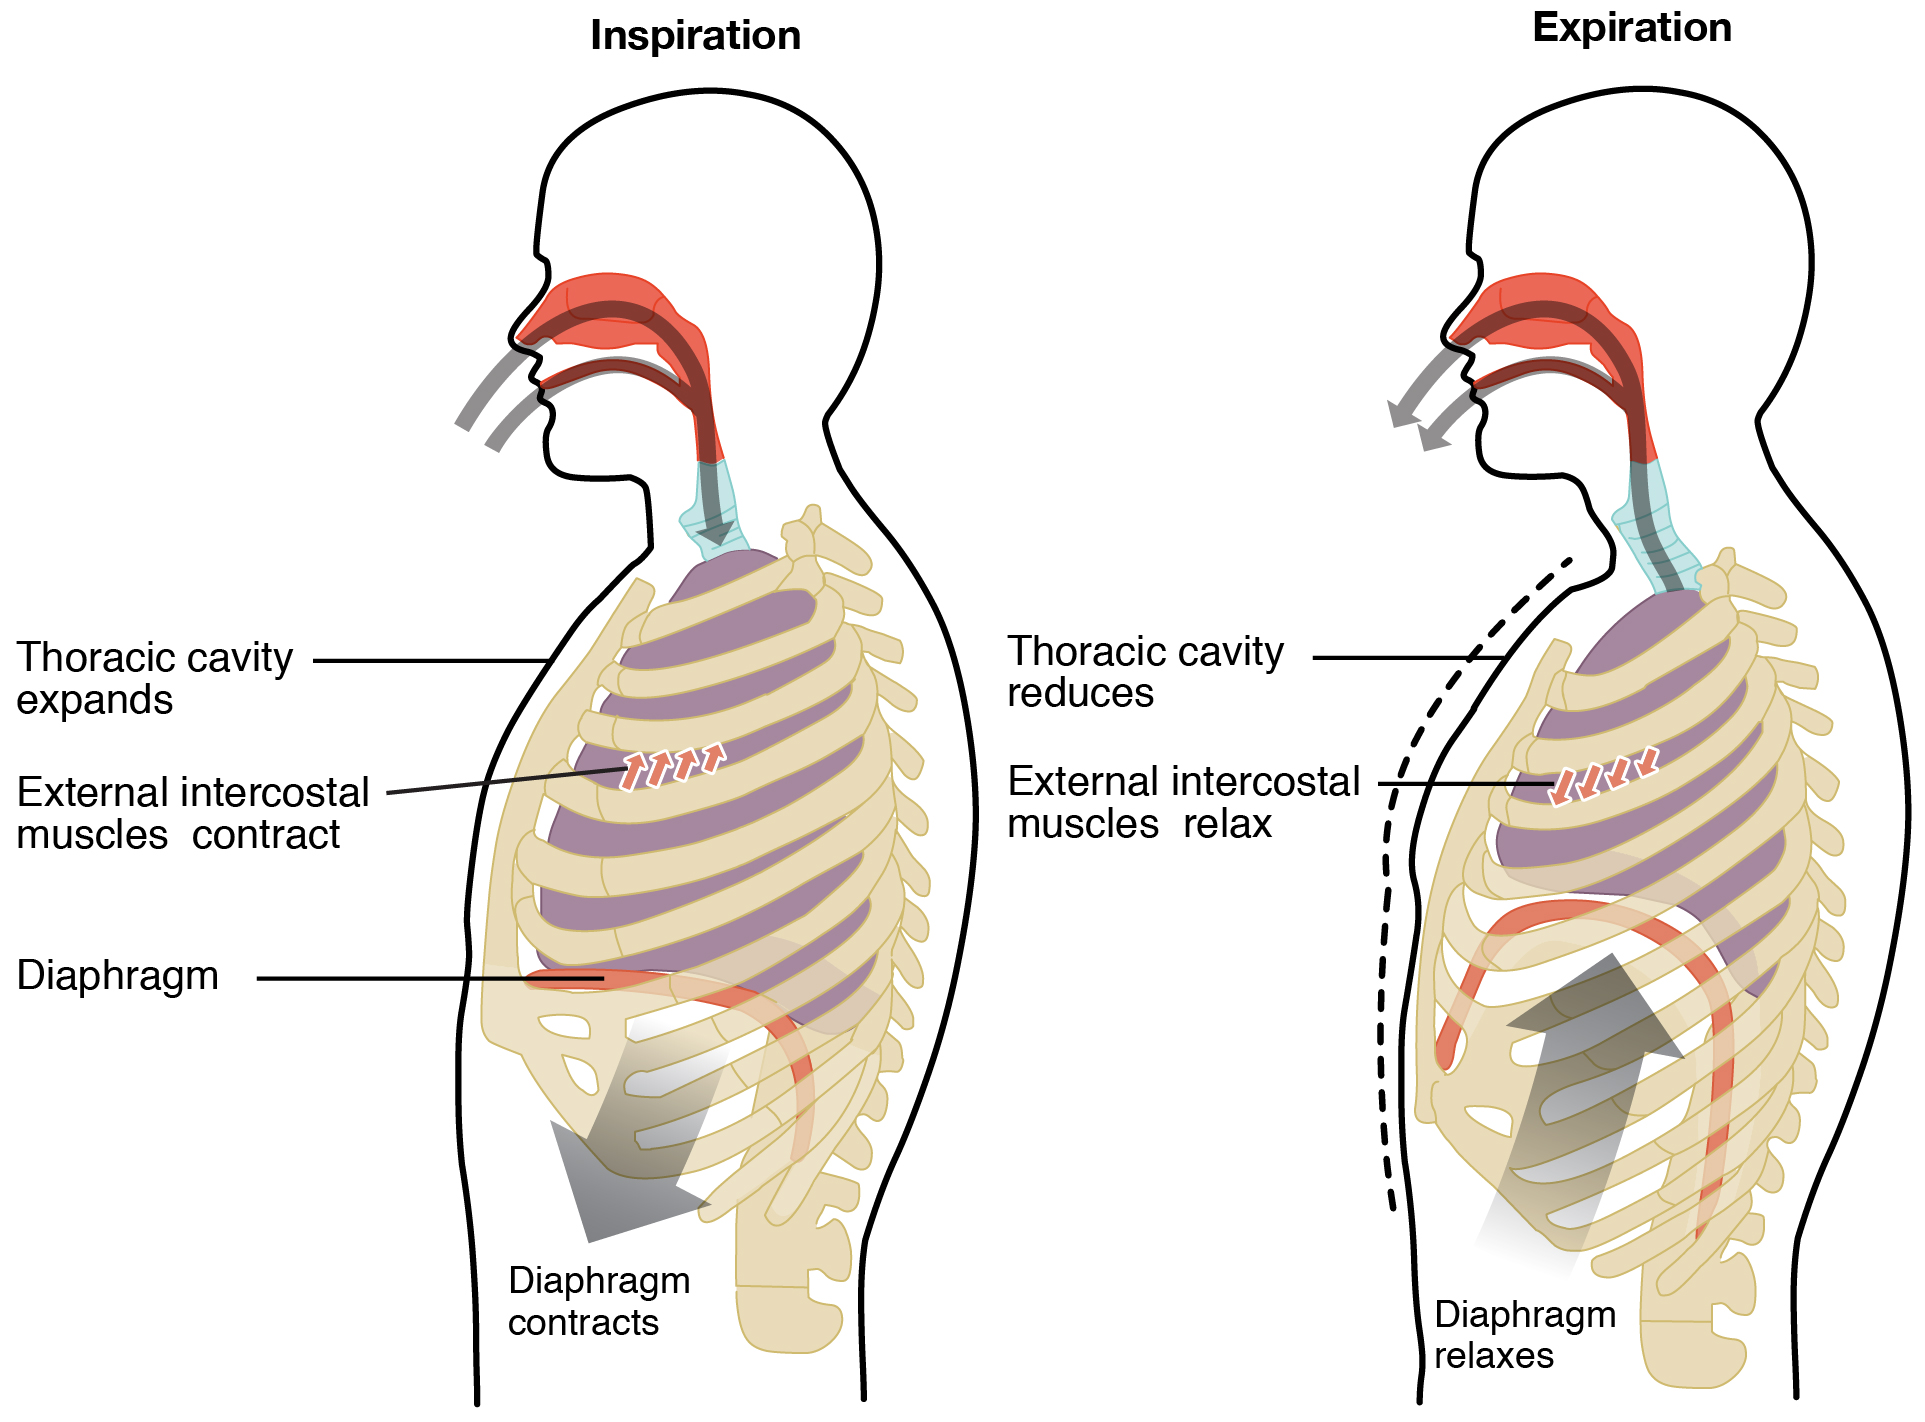

eupnea – also known as quiet breathing or the resting respiration is the normal breath. Here the process is completely passive and engages the elastic recoil of the lungs. In comparison to eupnea, apnea is the absence of respiration, dyspnea is diffcult respiration, bradypnea is slower respiration, and trachypnea is fast respiration.

Emphysema – With age there are various structural, functional and immunological changes that take place within the respiratory system. The anatomical changes include thoracic spine and chest wall distortion leading to impairment in the respiratory system and heavier breathing load. Due to the loss of its supporting structures, the lung parenchyma faces “senile emphysema” i.e., dilation of air spaces. In addition to that, the airway clearance needed for effective cough is also hindered due to the loss of strength in the respiratory muscles.

Elastcitiy (compliance) – Aging is strongly associated with a significant decrease in elastic recoil and fibrous strength. With age, there is inevitable reduction in the thoracic compliance and augmentation in lung compliance. Thoracic (chest wall) compliance regulates the elastic load during inhalation whereas the lung compliance regulates the rate and force of exhalation. With aging there are significant structural changes to the thoracic spine and cage which ultimately leads to depletion in chest wall compliance.